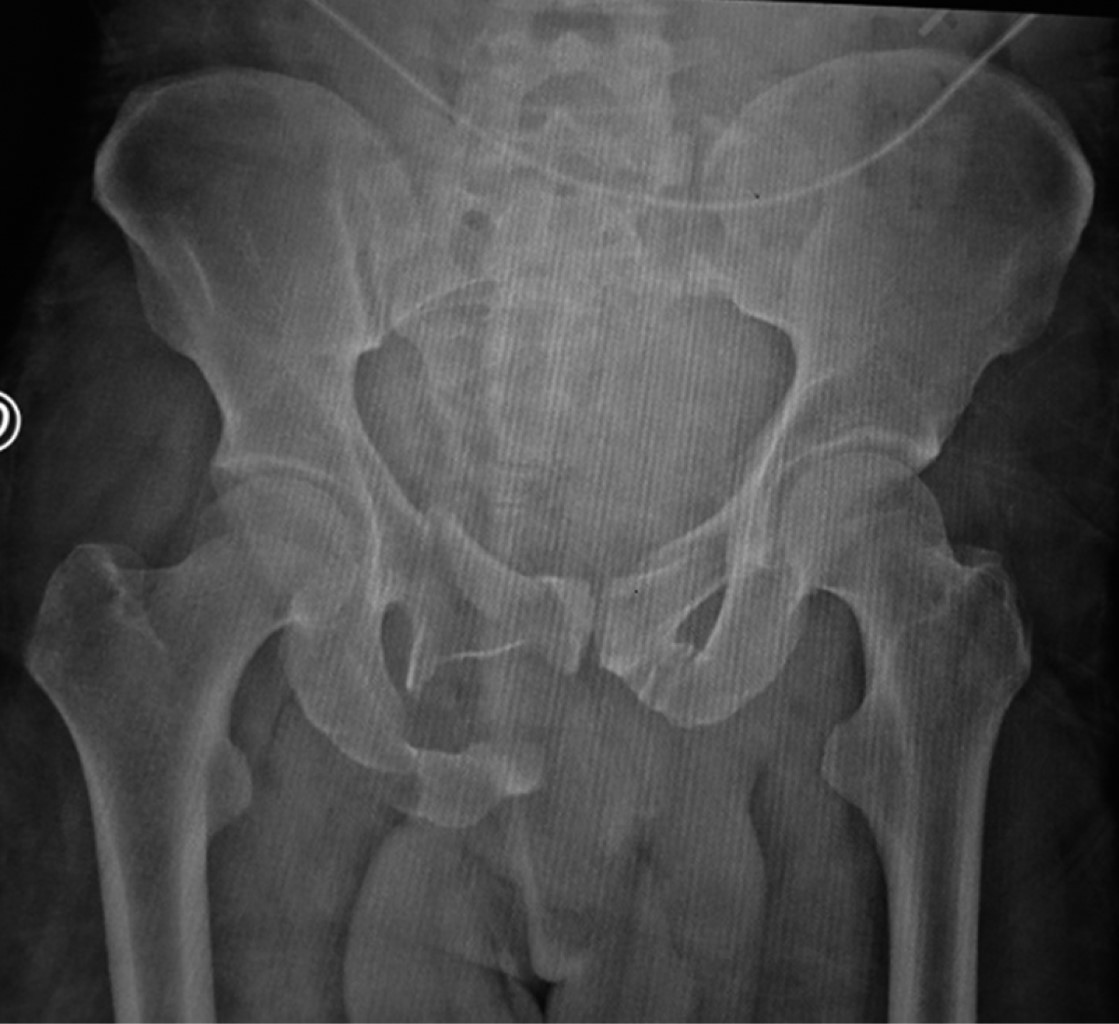

Las referencias anatómicas como cresta iliaca o región trocantérica pueden encontrarse alteradas por la severidad de las lesiones y ser difíciles de identificar. Se recomienda el uso de intensificador de imágenes durante la colocación del dispositivo en proyecciones anteroposterior, entrada y salida de pelvis y proyecciones oblicua alar y obturatriz (Figura 2).

Se colocan compresas o un campo en la región anterior de los muslos y del abdomen para evitar el choque directo del clamp y evitar lesiones por presión (Figura 5). No debe movilizarse o levantar al paciente del clamp, situación que es común por la falta de conocimiento del personal paramédico a cargo del paciente. Se realiza una radiografía de control en proyección anteroposterior de la pelvis para verificar la posición de los clavos y la reducción de la lesión (Figura 6).